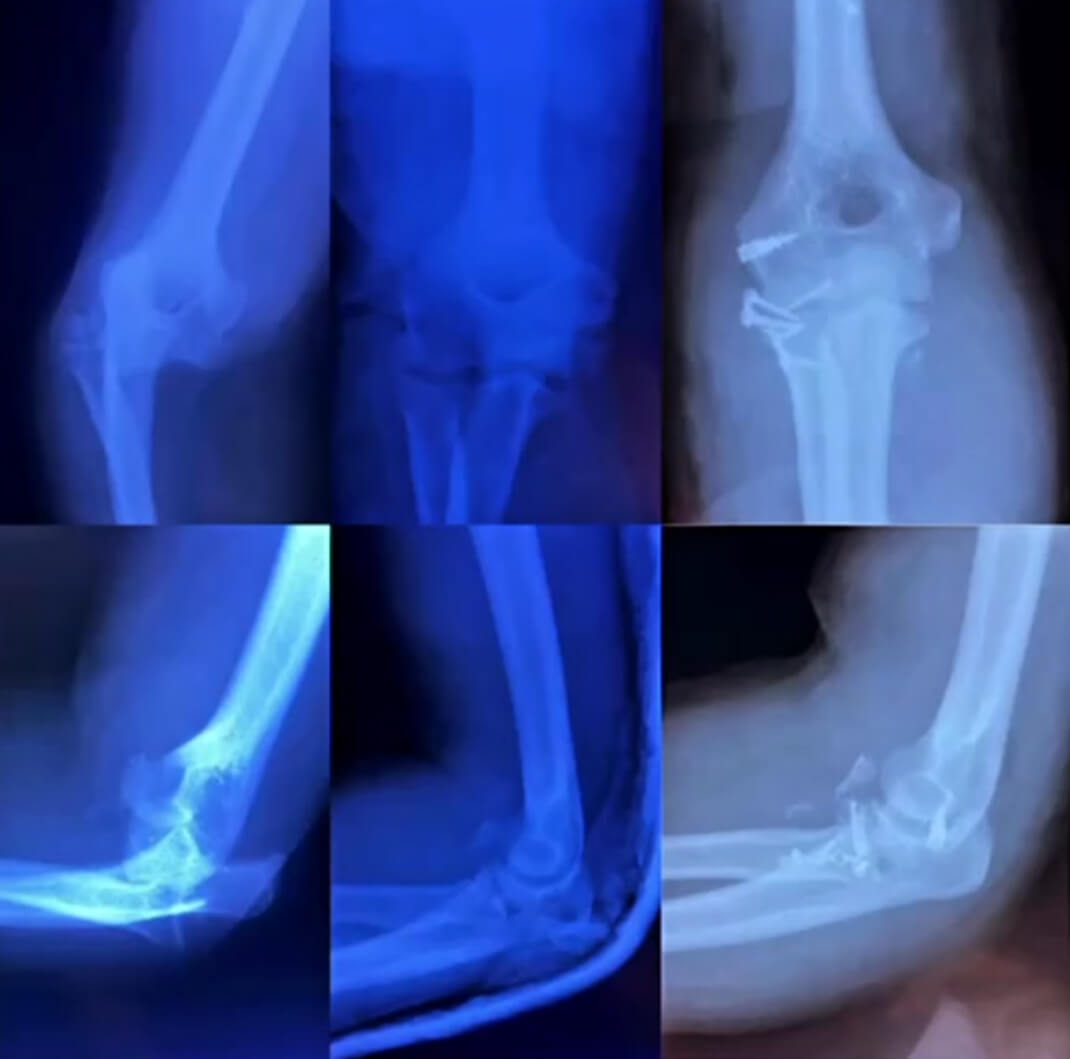

Fracturas de codo - Fracturas de olécranon: En el cúbito podemos presentar fracturas a nivel del olécranon que en donde se articula el húmero distal para permitir movimiento en flexión y extensión.

Fractura de Gartland desplazada: Las fracturas de Gartland son fracturas supracondíleas de húmero distal que ocurren en pacientes pediátricos (niños), estas pueden ser tratadas con un yeso o incluso necesitar cirugía para reducir y fijarla + un yeso.

Luxación de codo AP: Ciertos accidentes pueden ocasionarnos que el codo se “safe” esto consiste en la dislocación o luxación del húmero distal del olécranon y de la cúpula radial. En esta radiografía vemos como se observa desde frente la lesión, y en la siguiente →

Luxación de codo LATERAL: observamos cómo se diagnóstica la luxación de codo en una radiografía desde perfil.

Luxación + fractura de cúpula radial: en estos casos se encuentra dislocado el codo y asociado una fractura de la cabeza de radio; debe primero reducir la luxación para determinar el tipo de tratamiento que se puede dar a la cúpula radial.